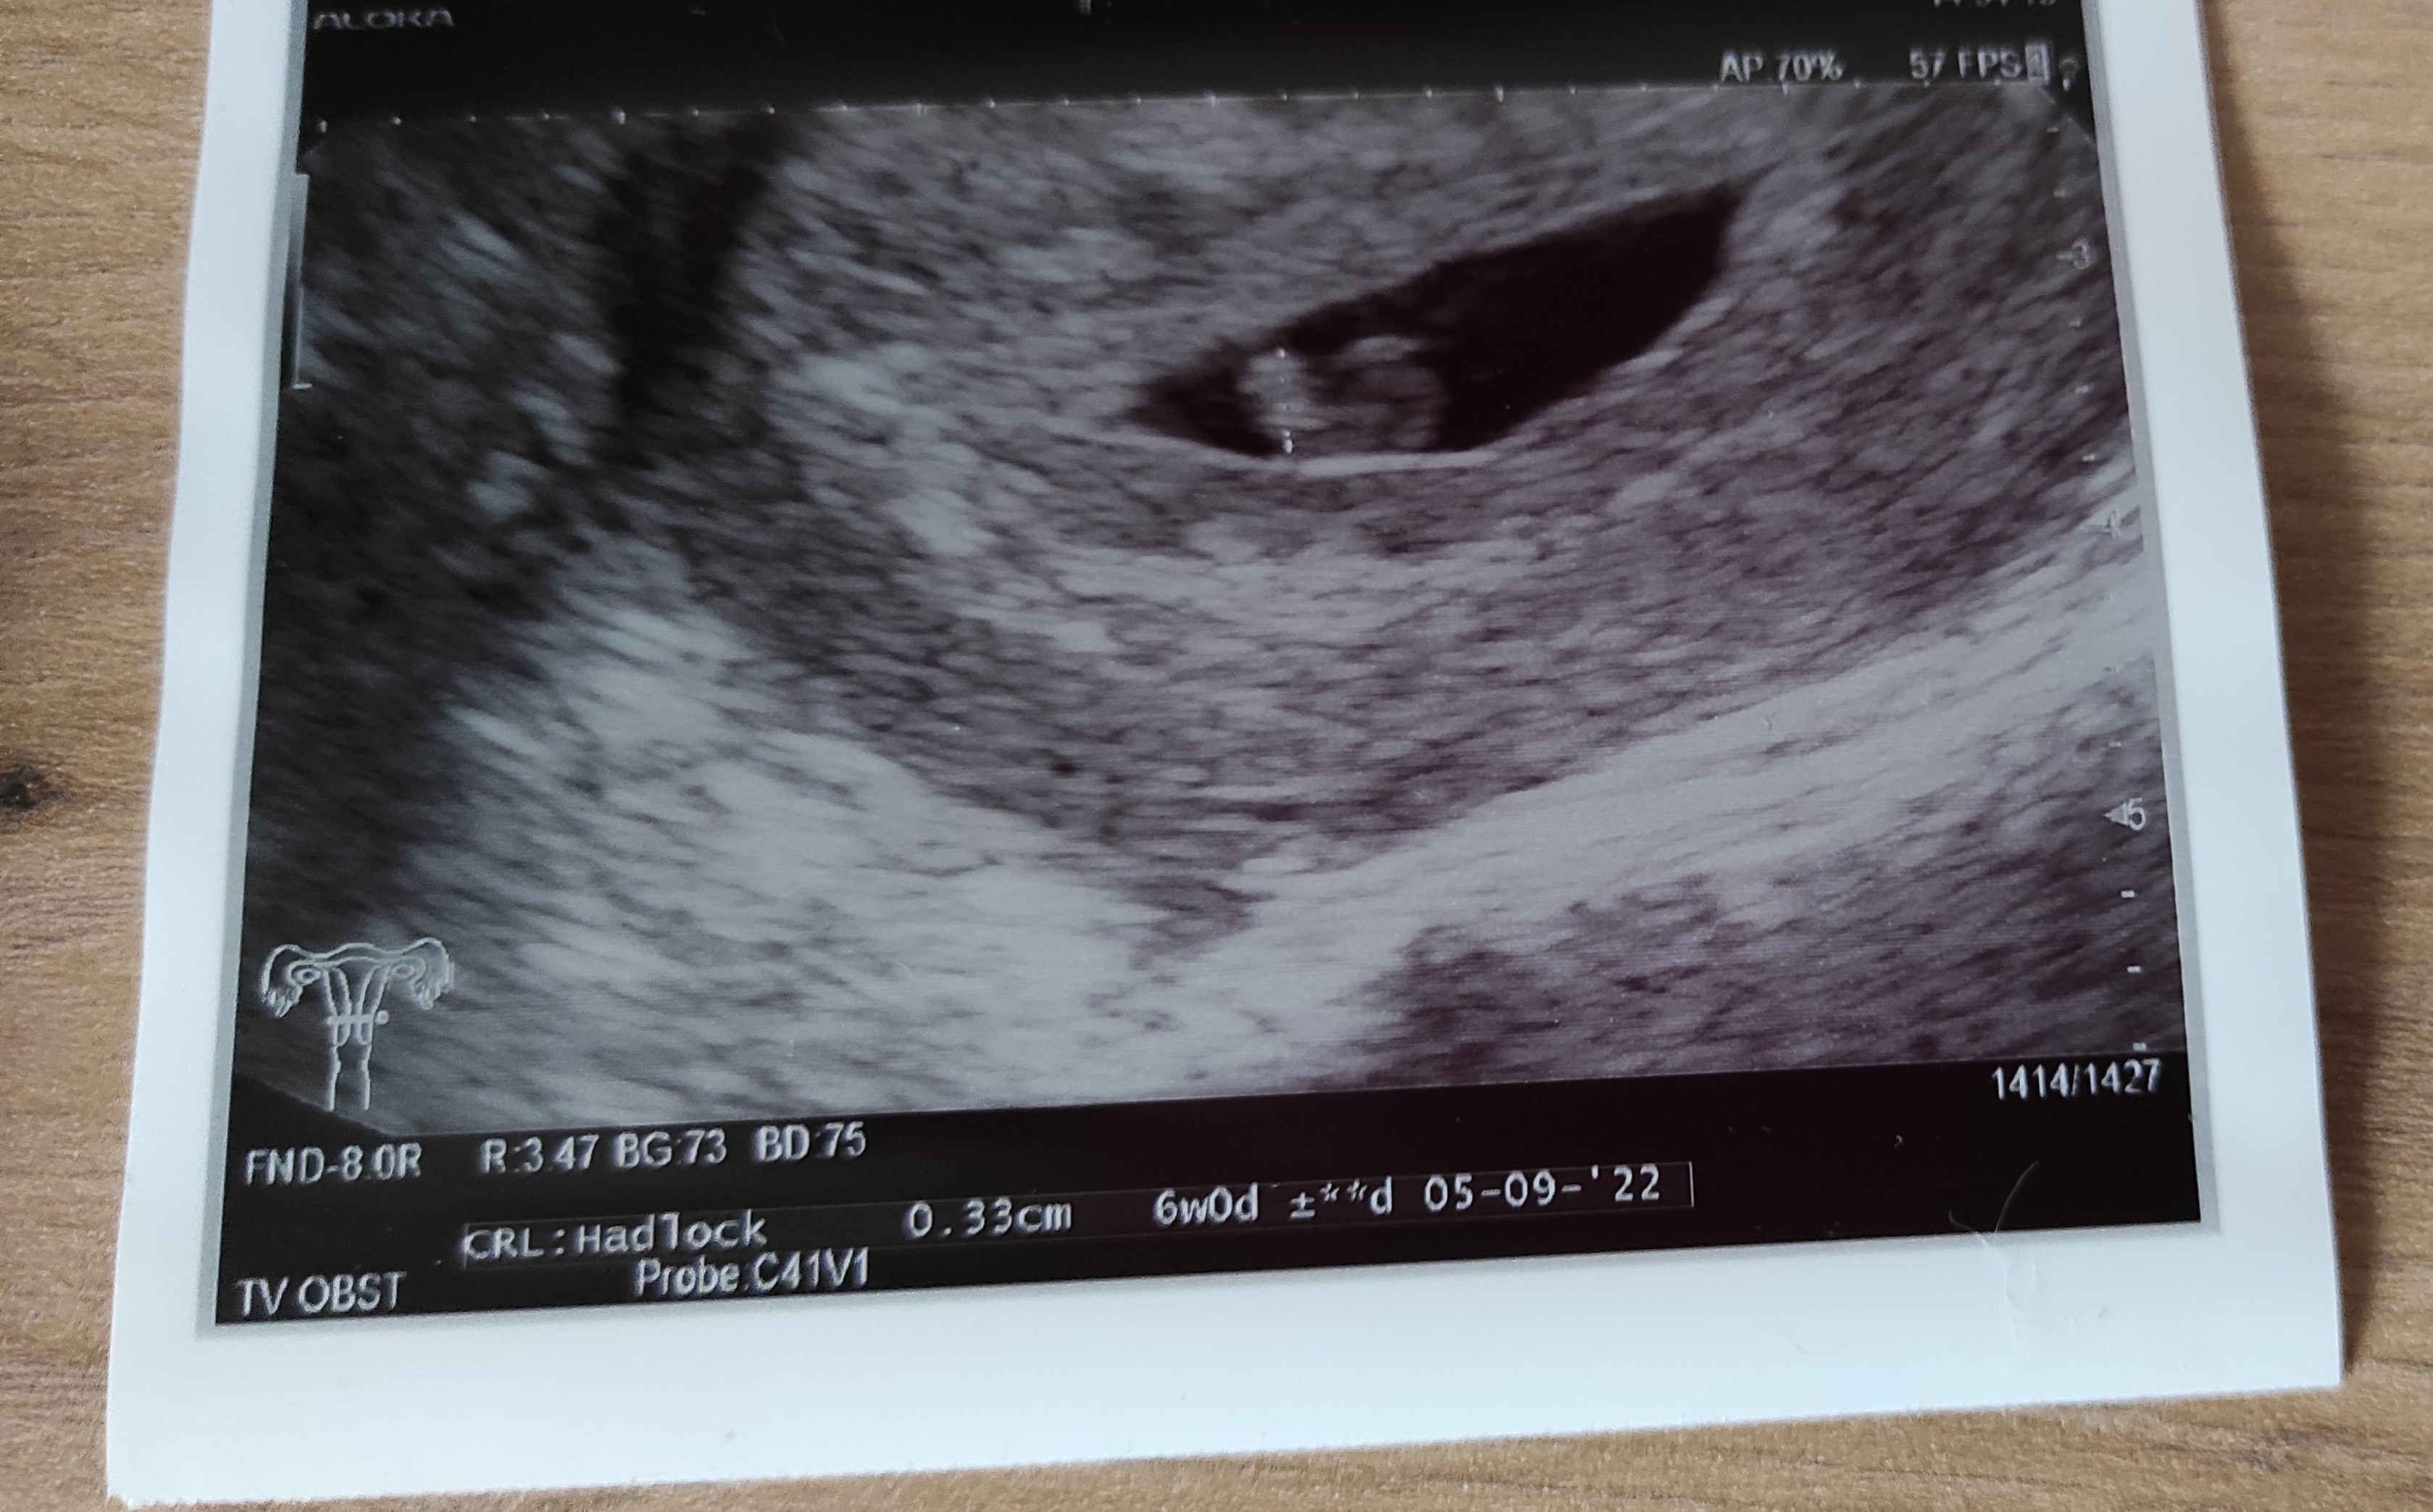

A tu moja fasolka z poniedziałku. Z USG to był 6 tydzień, aplikacja wtedy wskazywała 6t5d.

Serduszko biło jak szalone. :)